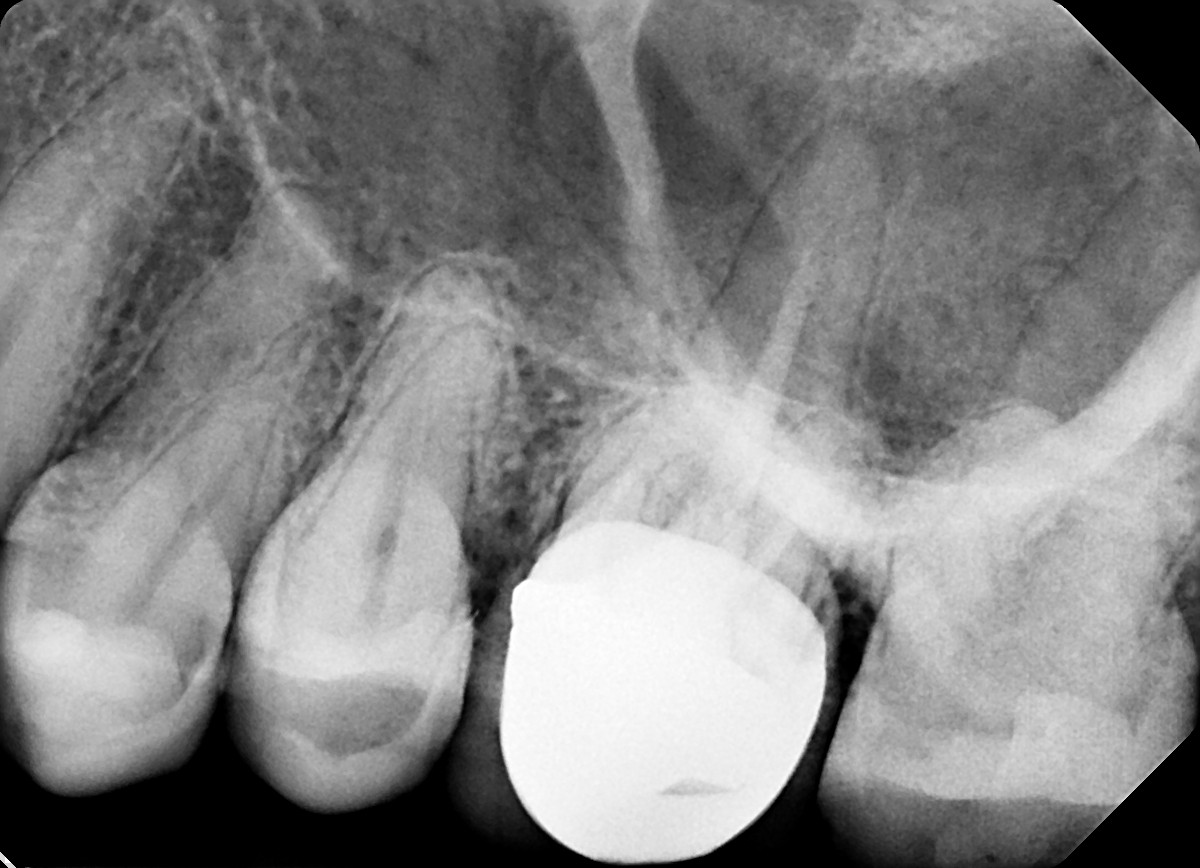

7. What option can explain the crown of the tooth #2.1?

11. What option can be selected for the crown over the tooth # 2.6?

30. What option can be selected for the crown over the tooth # 1.6?